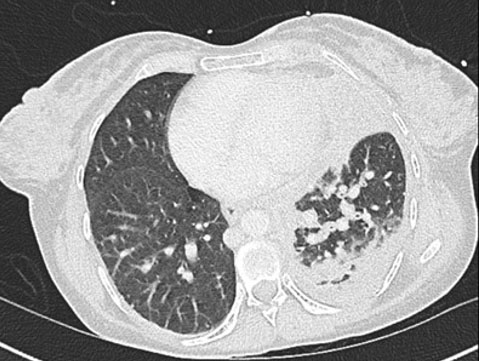

She was admitted to the high dependency unit (HDU) for monitoring following her drain insertion and pain management, requiring significant amounts of analgesia including patient-controlled analgesia, gabapentin, lidocaine patches, and ibuprofen. A computed tomography (CT) of the thorax performed five days later revealed extensive inflammatory changes in the left hemithorax, with left pleural thickening, loculation and hyperenhancement (Figure 2). Multiple enlarged anterior and middle mediastinal nodes were also noted. The pleural effusion reaccumulated four days post-chest drain removal. Interventional radiology inserted a new chest drain. The pleural fluid analysis was consistent with an exudate [protein 40 g/L, glucose 4 mmol/L, lactate dehydrogenase (LDH) 610 IU/L], and was negative for mycobacterium. Cytology revealed an adenocarcinoma of likely lung primary, which was positive for BerEP4, CK7, MNF116, and CEA; negative for TTF1, CK20, calretinin, and WT1. Six days later she underwent an endobronchial ultrasound (EBUS), which confirmed an adenocarcinoma. PD-L1 was negative (0%) on immunohistochemistry. Molecular diagnostics on the endobronchial ultrasound (EBUS) sample revealed a KRAS-G12D mutation with a variant allele frequency (VAF) of 45% [EGFR and BRAF were wild-type (WT)]. Fusion testing of the RNA panel failed to provide a result. She had spontaneous rupture of her membranes later that day and underwent a breech vaginal delivery at 30+4 weeks’ gestation. Her baby weighed 1545 g at birth (between the 50th and 75th centile), Apgar scores were 9 and 10 at one and five minutes post-delivery respectively and baby was admitted to the neonatal intensive care unit (NICU).

Figure 2: CT thorax with contrast revealing extensive inflammatory changes in the left hemithorax, with left pleural thickening, loculation, and hyperenhancement, as well as multiple enlarged lymph nodes.